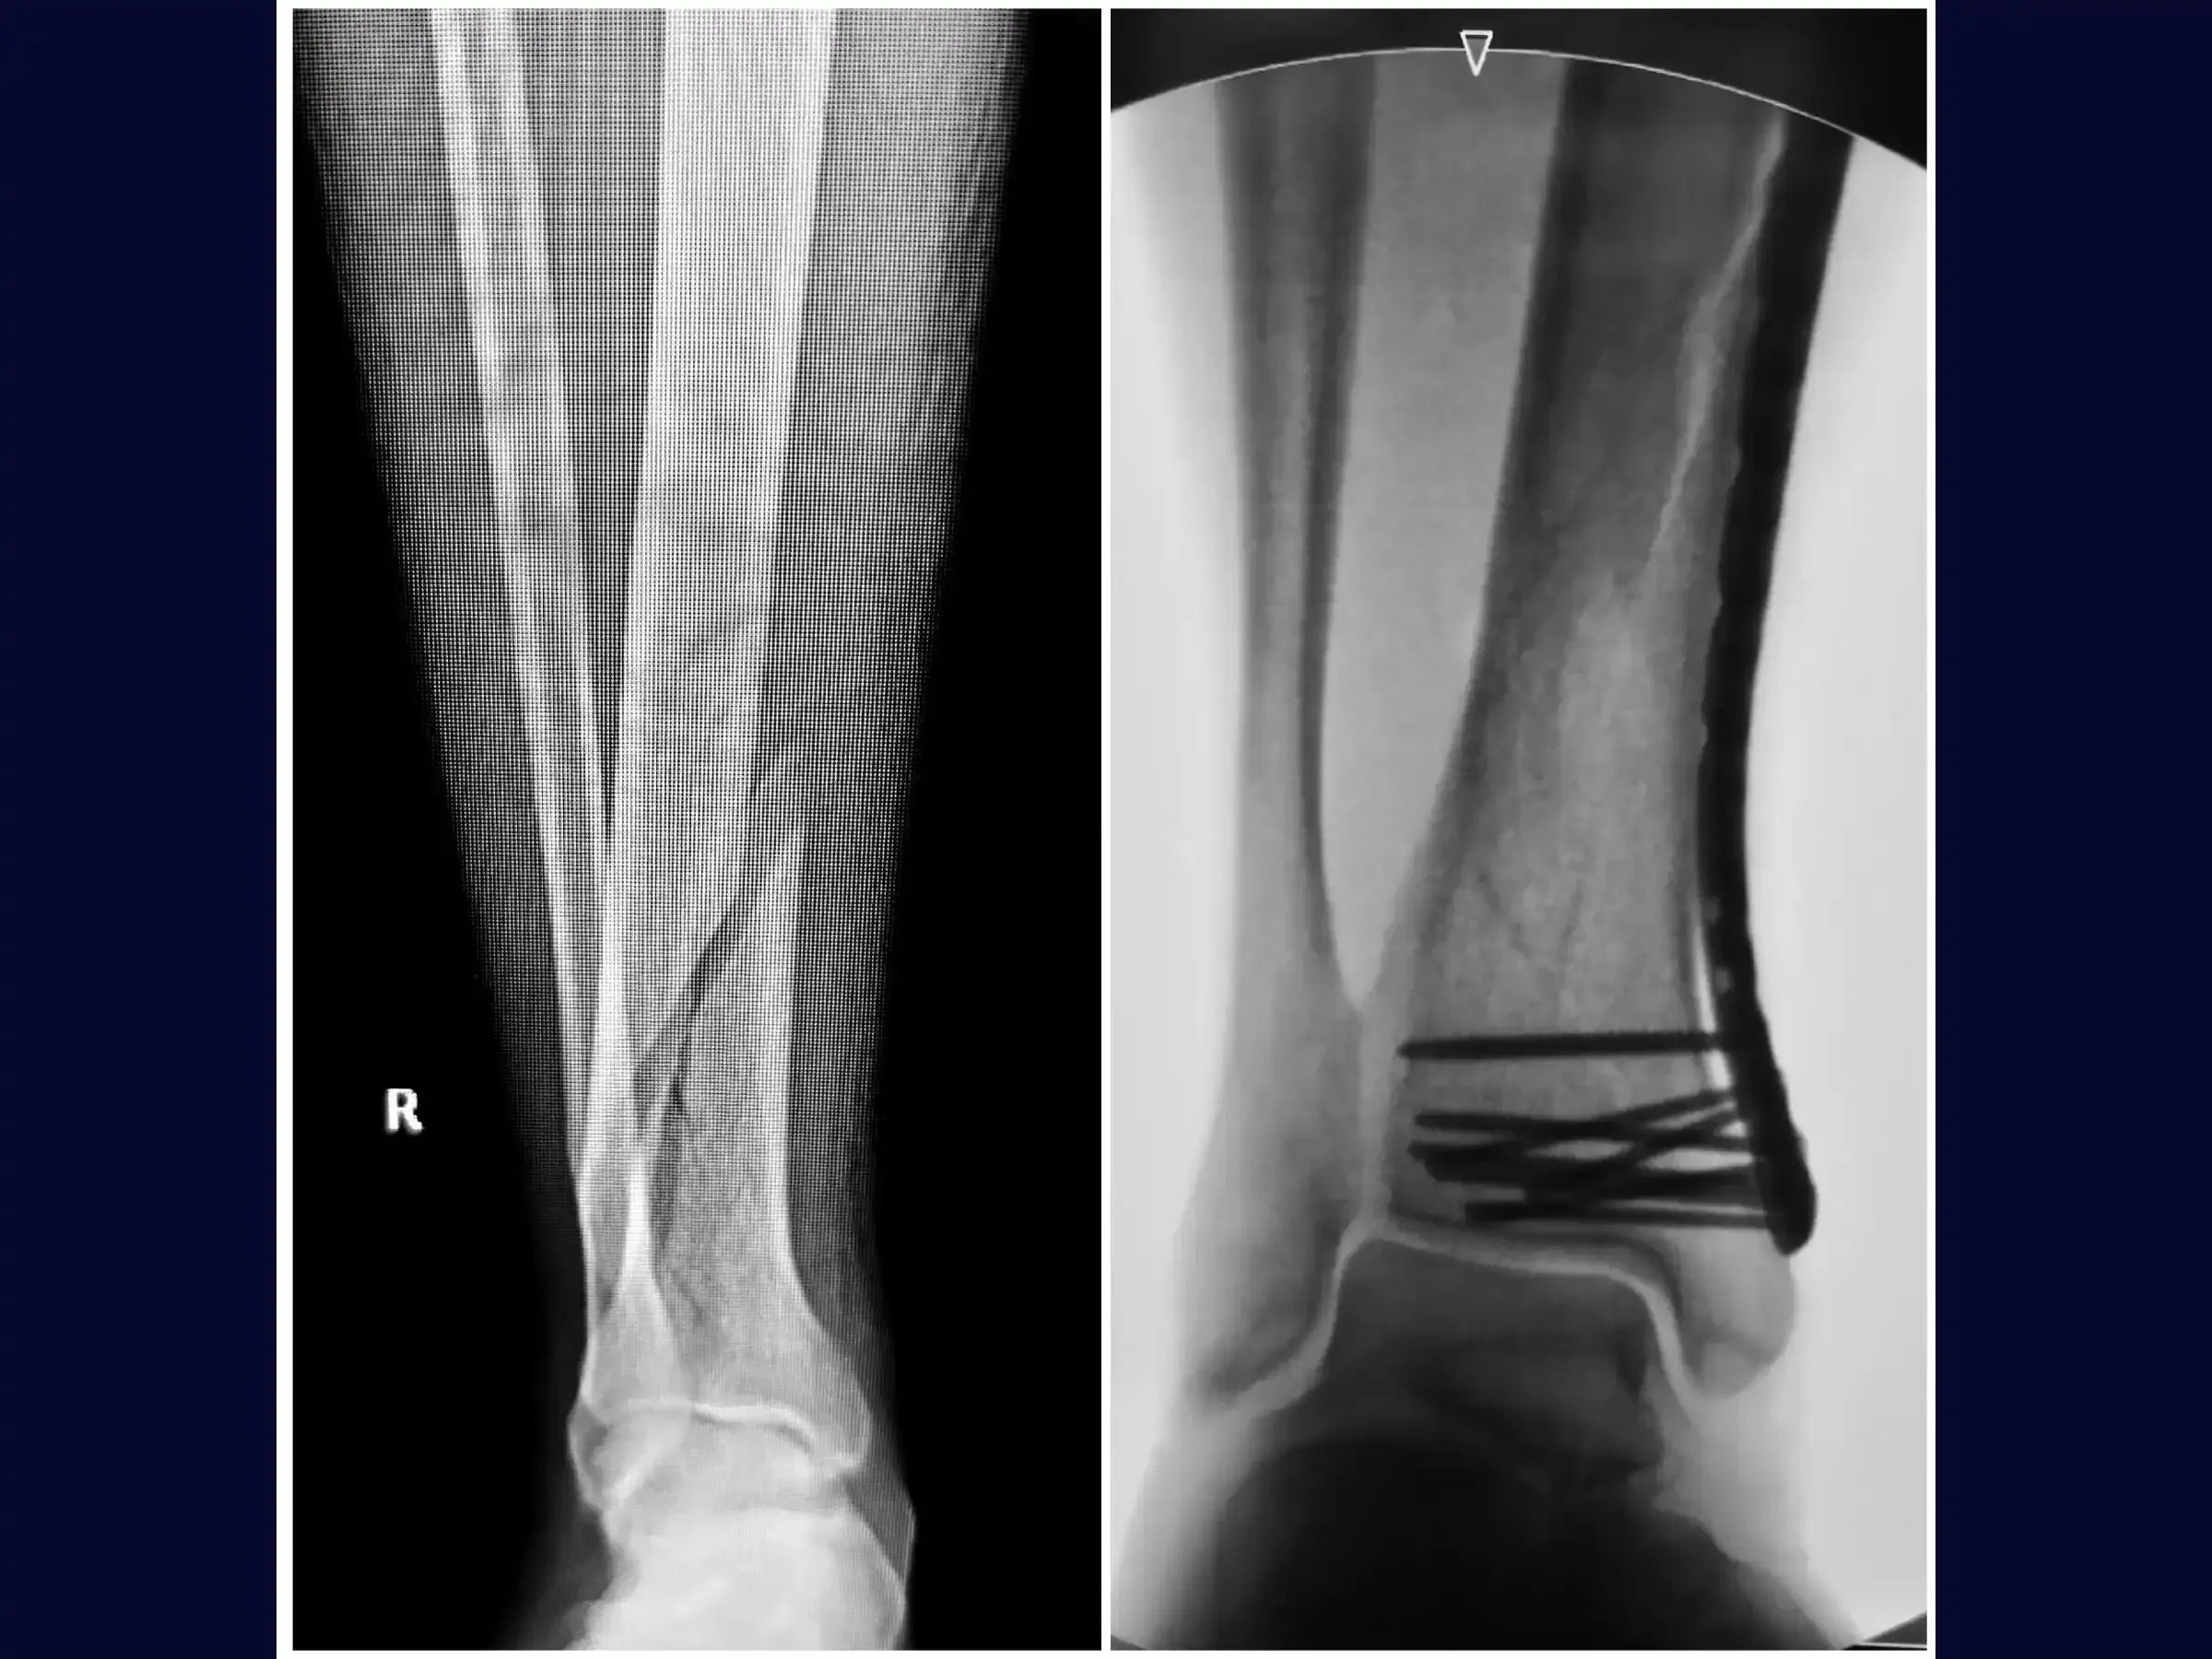

- Surgical treatment of diaphyseal tibial fractures with long oblique and spiral patterns.

- Optimized Preoperative Planning: Assessment of diaphyseal tibial fractures and associated fibula fractures through X-ray and computed tomography for precise planning.

- Safe Percutaneous Reduction: Methodology for obtaining preliminary and final percutaneous reduction with reduction clamps, including traction and rotation maneuvers of the ankle, accompanied by an image intensifier.

- Definitive Fixation and Optimization of Osteosynthesis: Procedure for drilling and inserting distal screws in the distal third of the tibia, with the plate positioned snugly against the bone to avoid irritation of the medial malleolus.Insertion of an additional screw near the fracture focus to optimize energy distribution and balance the osteosynthesis. Finalization with proximal screws.

- Comprehensive Final Assessment: Confirmation of anatomical reduction, sufficient number of screws, proper positioning of the long plate, relative stability, and maintenance of external rotation similar to the contralateral side.